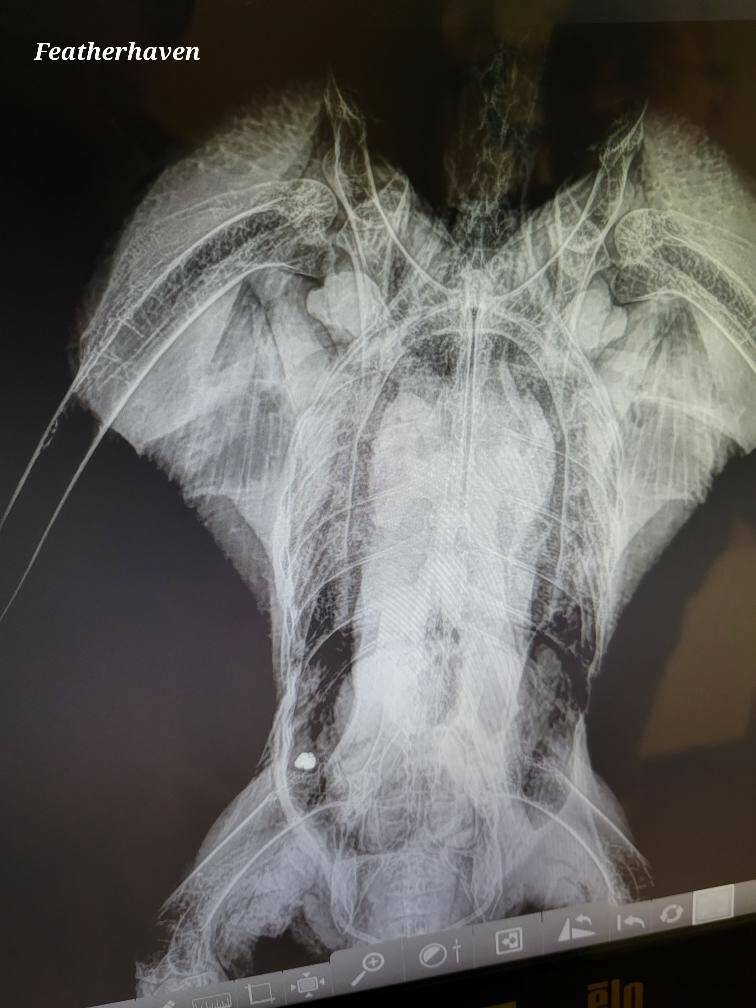

“We found… a wound in the right ventral shoulder, fresh,” Ward said. “We did a series of X-rays, which showed [a] bullet in the caudal abdomen on the right side.”

The bullet was deformed, which can be caused when it comes into contact with soft tissue, Ward continued — but more than likely, it hit the spine, causing the eagle to be paralyzed from the proverbial waist down.

It was determined by Ward and two other experts that the chances of the eagle recovering was extremely low — “way less than 5%,” he said, given that nobody present was specialized in bald eagle spinal surgery — so it was humanely euthanized that evening.